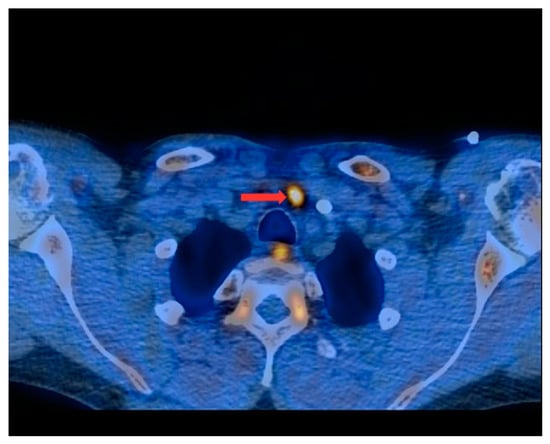

Figure 2.

PET/CT with [11C]MET—axial projection. Visible focus of increased radiotracer accumulation (red arrow) corresponding to the parathyroid gland in front of the trachea, at the left-hand side of the midline of the body.